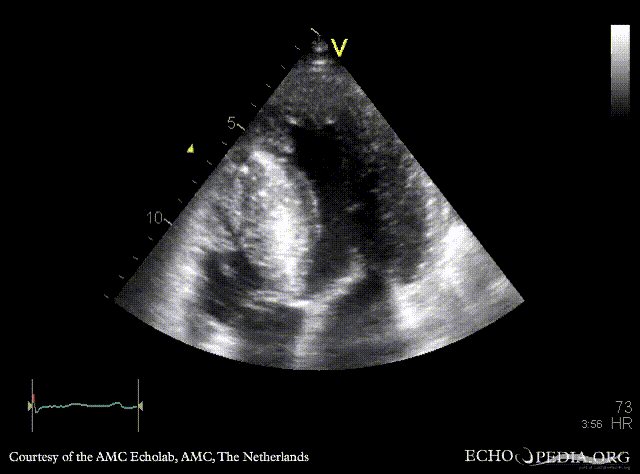

A4CH: systolic obliteration of left ventricle, SAM of AMVL A4CH with Color Doppler: high velocity turbulent flow in LVOT and in the middle of left ventricle